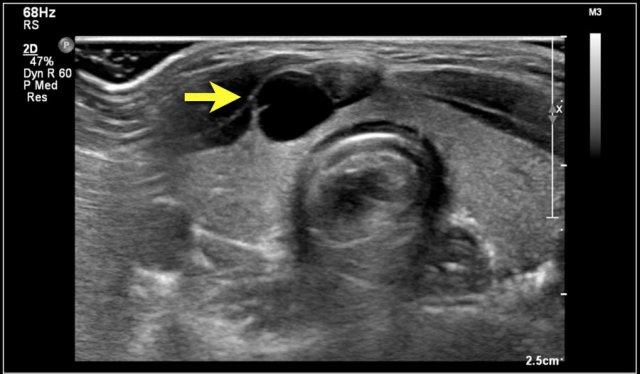

Two-year-old boy with a progressive swelling in the neck. No effect of antibiotics. An atypical Mycobacterium infection (avium) was confirmed. The anechoic parts (arrow) in the node are often seen in atypical Mycobacteria infection.